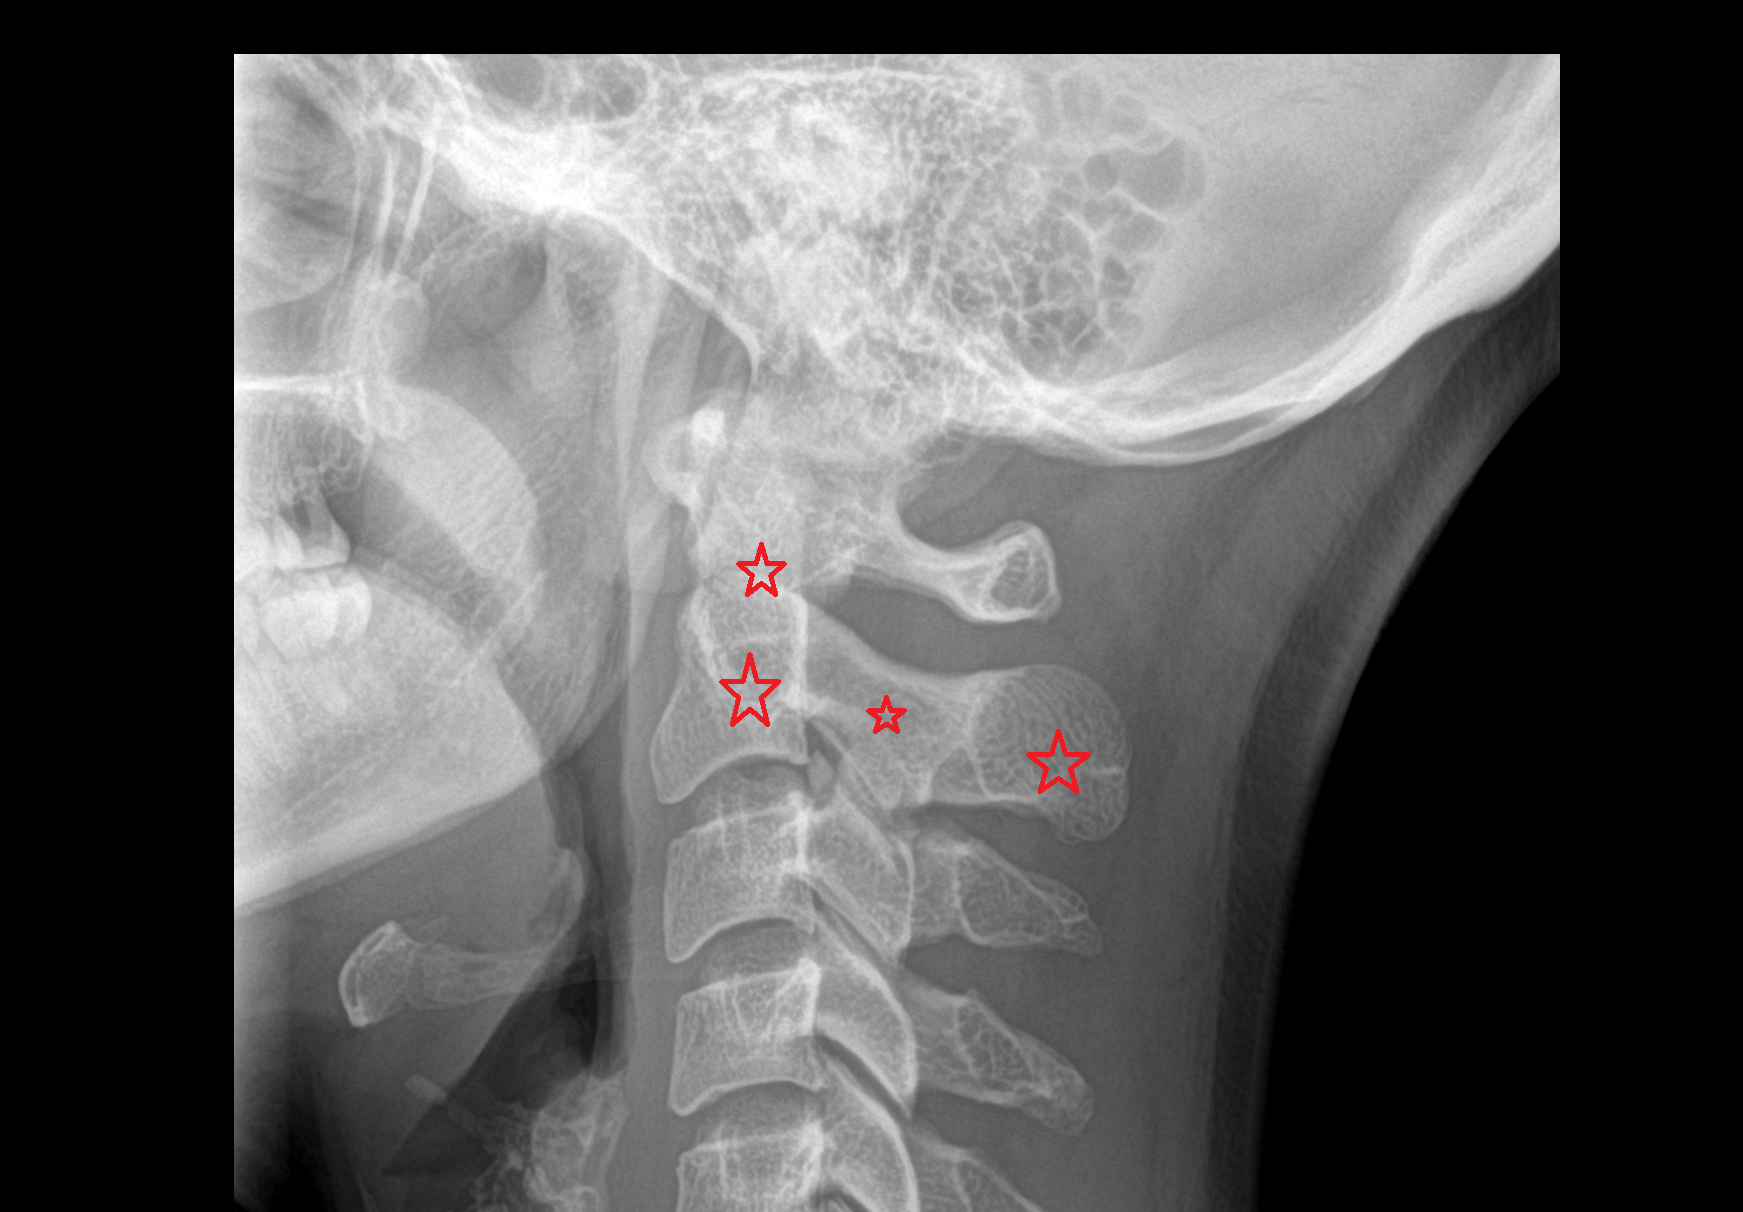

- Axis (C2 vertebra)

- C3–C4 intervertebral disc

- Facet joint of vertebra (Zygapophyseal joints)

- Atlantooccipital joint

- Lateral atlantoaxial joint

- Anterior longitudinal ligament

- Posterior longitudinal ligament

- Ligamenta flava (Ligamentum flavum)

- Interspinous ligament